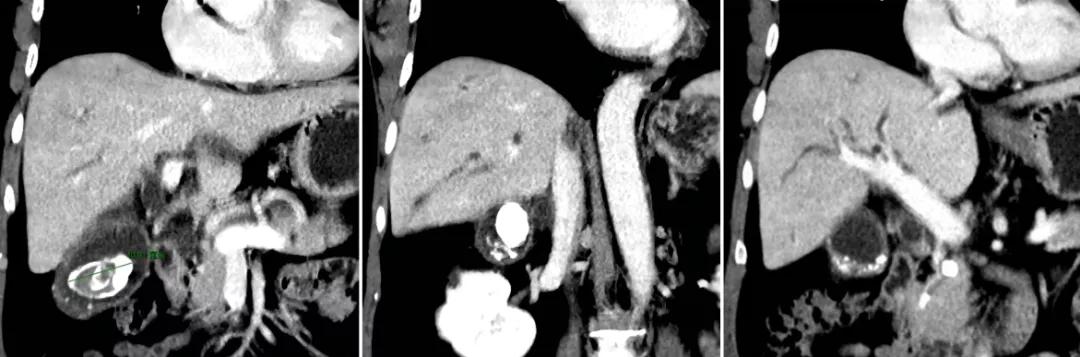

47岁男性,胆囊结石多年,未予重视。与朋友聚餐后突发腹痛并身目黄染急诊入院,检查提示胆囊最大结石直径超过4cm,胆总管下端小结石堵塞致肝内外胆管扩张,总胆红素超过300μmol/L(正常值为小于21μmol/L),行“腹腔镜胆囊切除+胆总管切开探查取石+T管引流”,术后症状缓解,黄疸逐步消退。